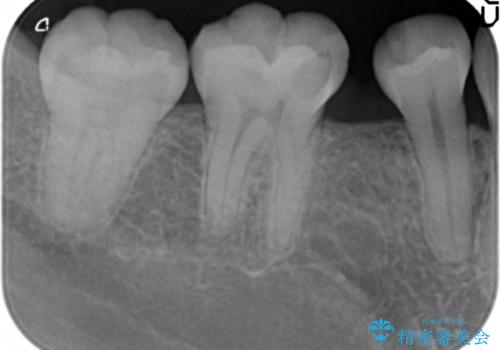

矯正せずに早く治したいという強いご希望とう蝕があることから、セラミッククラウンによる補綴治療で隙間を閉じることにしました。

クラウンの種類:オールセラミッククラウン スタンダード